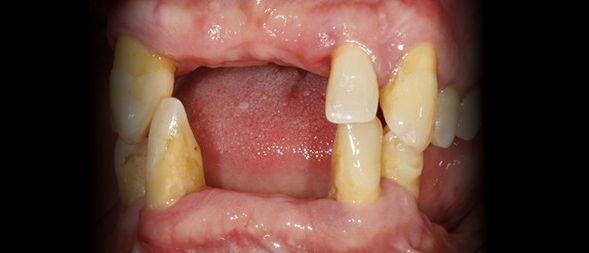

Caso clínico sobre Estética Dentária